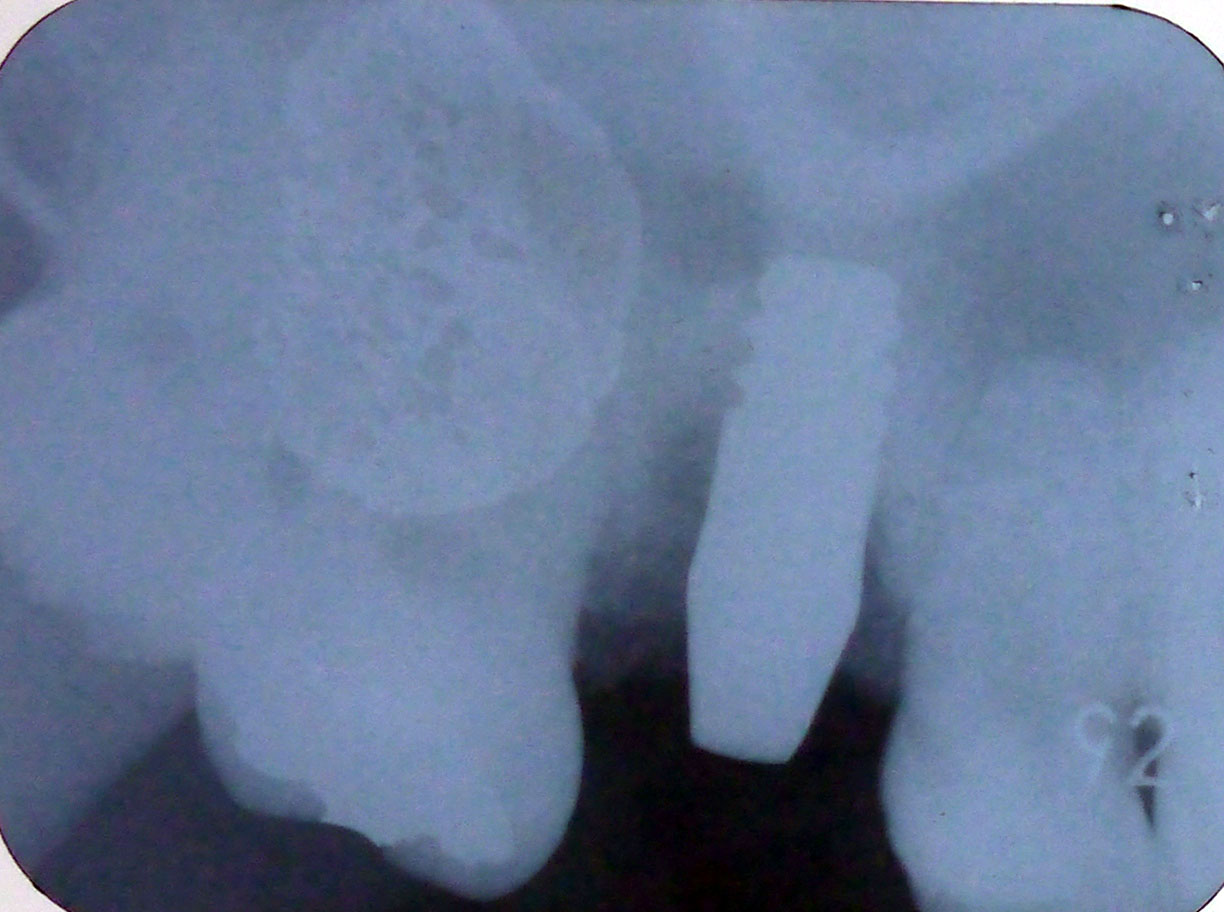

レントゲン画像1

平成24年3月30日の手術直後のレントゲン画像

オオダチメソッド(スパーソケットリフトにて)上顎洞下底の粘膜が持ち上げられている